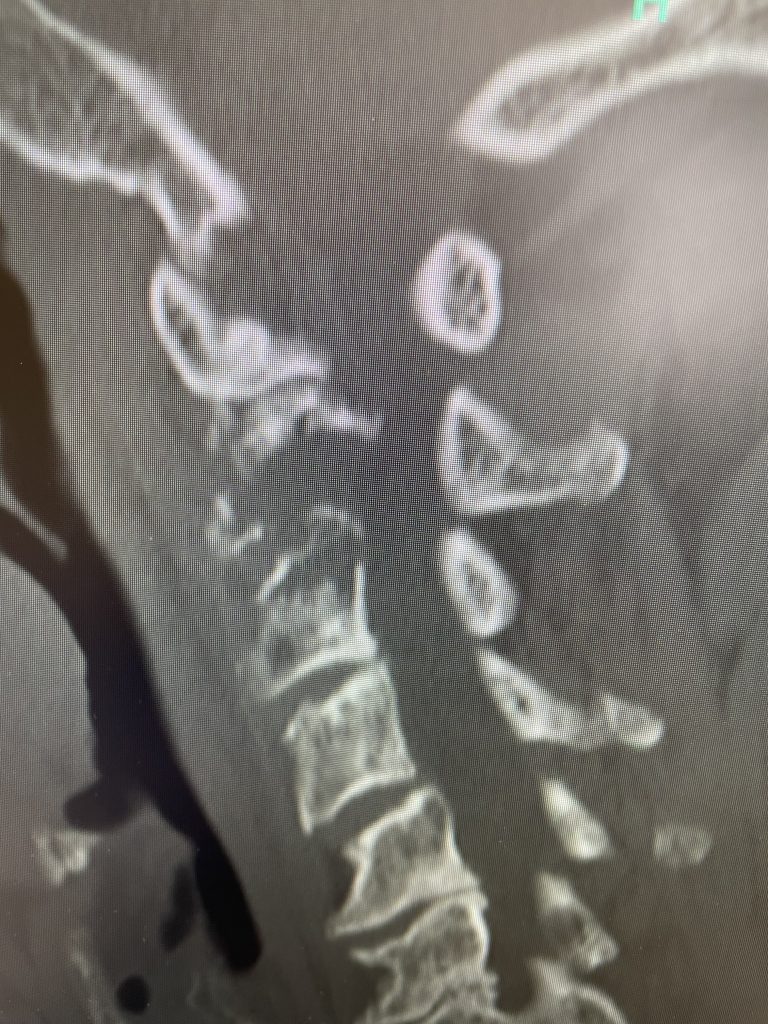

After several months he represented with worsening neck pain and placed in a hard collar. He had a repeat CT scan which showed some progression of disease now more affecting the C3 vertebral body (Fig 11). The patient had flexion extension x-rays which showed stability. The patient was referred to pain management for better control. He was placed in a hard collar. Given the progression of disease after radiation, three columns of the spine affected, progression of neck pain, potential for collapse of the bone and retropulsion into the canal causing quadriplegia, surgical stabilization was offered to the patient. Given the poor bone quality, as one can assume that the multiple myeloma could extend to other adjacent bones, it is challenging to stabilize the patient with good fixation. Options would include stabilizing with hardware and fusion from C1 to C5 which would provide stabilization above and below the area of potential collapse. Another option would be to go from occiput to C5. This is a more morbid procedure and really severely limits head movement. Your “yes” and “no” movements are between your occiput and C2. Most people do not realize that sixty percent of your head and neck motion is between the occiput and C2. The rest is distributed amongst the other cervical vertebrae. If a fusion was carried up to C1, then the patient would not lose as much motion not to mention the significantly increased exposure and risk with an occipital-cervical fusion. The patient declined surgical treatment at this point knowing all the risks. He agreed to wear his collar. He was in better pain control. He will be followed closely.

Fig 2: Sagittal CT scan demonstrating progression of disease into C3 vertebral body